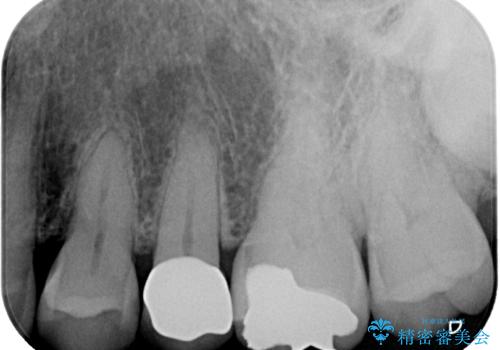

「他の歯も、せっかくなら精度の良いものに替えておきたい」とのご希望があり、

上顎左側第一大臼歯

下顎左側第一大臼歯

に入っていた保険診療の銀歯(メタルインレー)を、精度の良いゴールドインレーへやり替えを行いました。